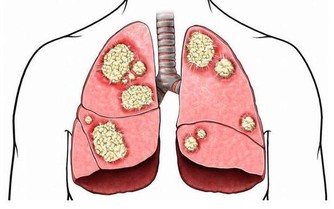

提到尿酸高,很多人第一時間想到的就是痛風,其實,尿酸高不僅會導致痛風,還會引發動脈硬化、糖尿病、腎結石,甚至誘發腎衰竭等等。也就是說,痛風只是高尿酸的所致危害的“冰山一角”。

研究發現:血尿酸水平每增加60維摩/毫升,新發糖尿病風險增加17%;高尿酸患者發生高血壓的風險增加81%,且血尿酸水平每增加60維摩/毫升,高血壓風險增加9%;高尿酸患者的腦卒中發生風險增加22%,腦卒中的死亡風險增加33%。

無症狀高尿酸血症:沉默的殺手!

通常情況下,人體每天產生的尿酸量與尿酸排泄量之間,能保持一種動態平衡。一旦尿酸生成過多,或排泄減少,就可能引起高尿酸血症。

在正常飲食狀態下,非同日兩次空腹血尿酸男性和絕經後的女性>420mol/L、非絕經期女性>360mol/L,即為高尿酸血症。

無症狀的高尿酸血症患者,尿酸水平也已超過正常值,只是由於尿酸鹽沒有沉積到關節或軟組織裡,因此沒有發生痛風關節炎、痛風石或尿酸結石等表現。只有在尿酸鹽在機體組織中沉積下來造成了損害後,患者才會出現痛風。

而且,無論是否出現關節疼痛等痛風症狀,高尿酸血症對人體的損害是一樣的,甚至可以說,正是因為沒有症狀而不會引起注意,反而更具危險性,就像沉默殺手。